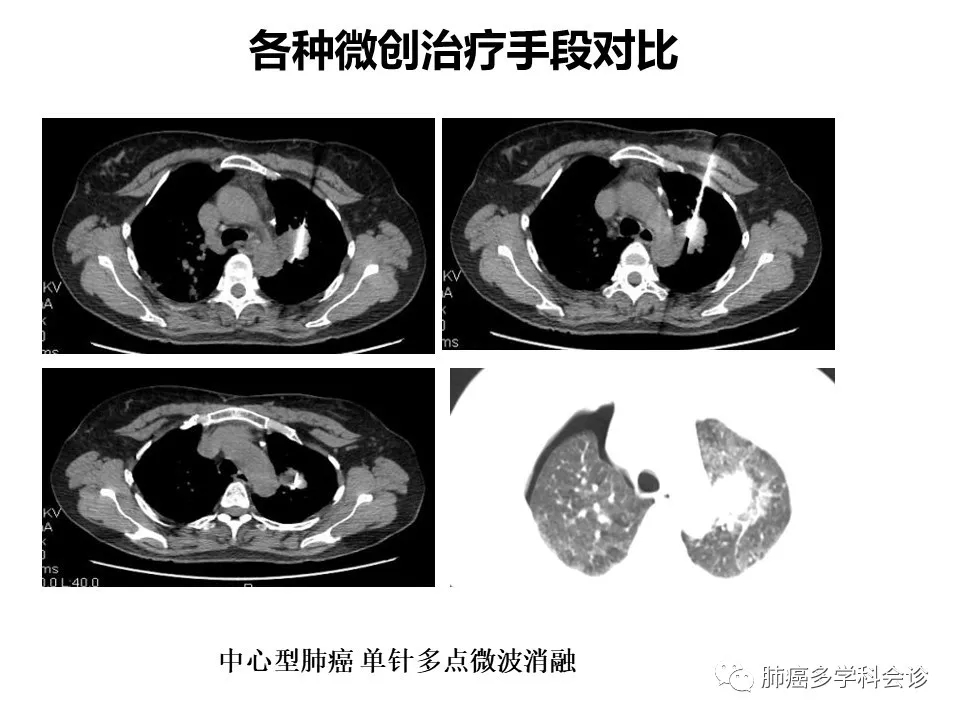

肺癌微创治疗时机的选择